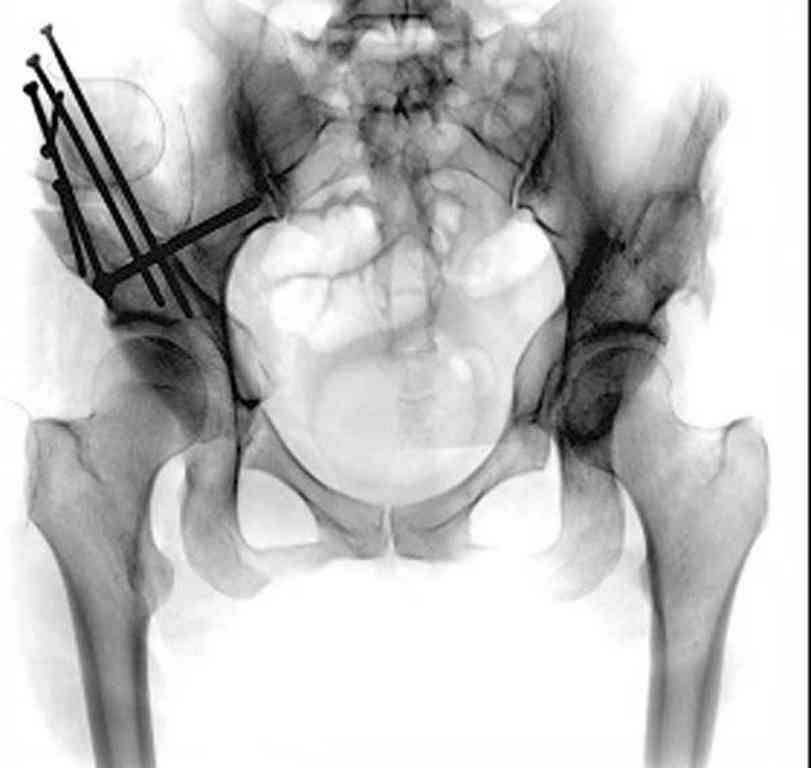

При более сохранном суставе от дальнейшего разрушения можно было бы сохранить только периориентацией нагрузки на сустав - Периацетабулярной Остеотомией .

Данный сустав в начальной стадии разрушения, но все-таки я бы сделал обзорный таз и отдельные снимки сустава в 30 градусной абдукции и аддукции. Также снимки с внутренней и наружной ротацией для оценки состояния головки бедра.

После участия в последней конференции "Вреденовские Чтения" в Ст. Петербурге, по представленным докладам, я убедился, что в территории СНГ очень мало специалистов энтузиастов, кто серьезно занимается патологией дисплазии. В большинстве те, кто занимается данной патологией, делают давно забытую тройную остеотомию таза, и доложенные результаты находятся далеко от идеала...

Только коллеги из Вреденовского Института начали работу по тематике сохранения тазобедренного сустава, остеотомия как альтернатива замене сустава. Надеюсь, что скоро в России многие последуют примеру Ст. Петербурга, и тогда уменьшатся цифры по протезированию у молодых.